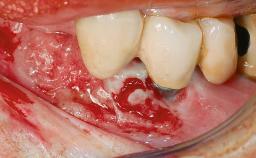

Peripheral Giant-cell Granuloma Associated with Peri-implant Tissues

Surgical SAC classification

SAC Level Advanced

Defining Characteristics More than three missing teeth to be replaced with an implant-borne prosthesis or prostheses